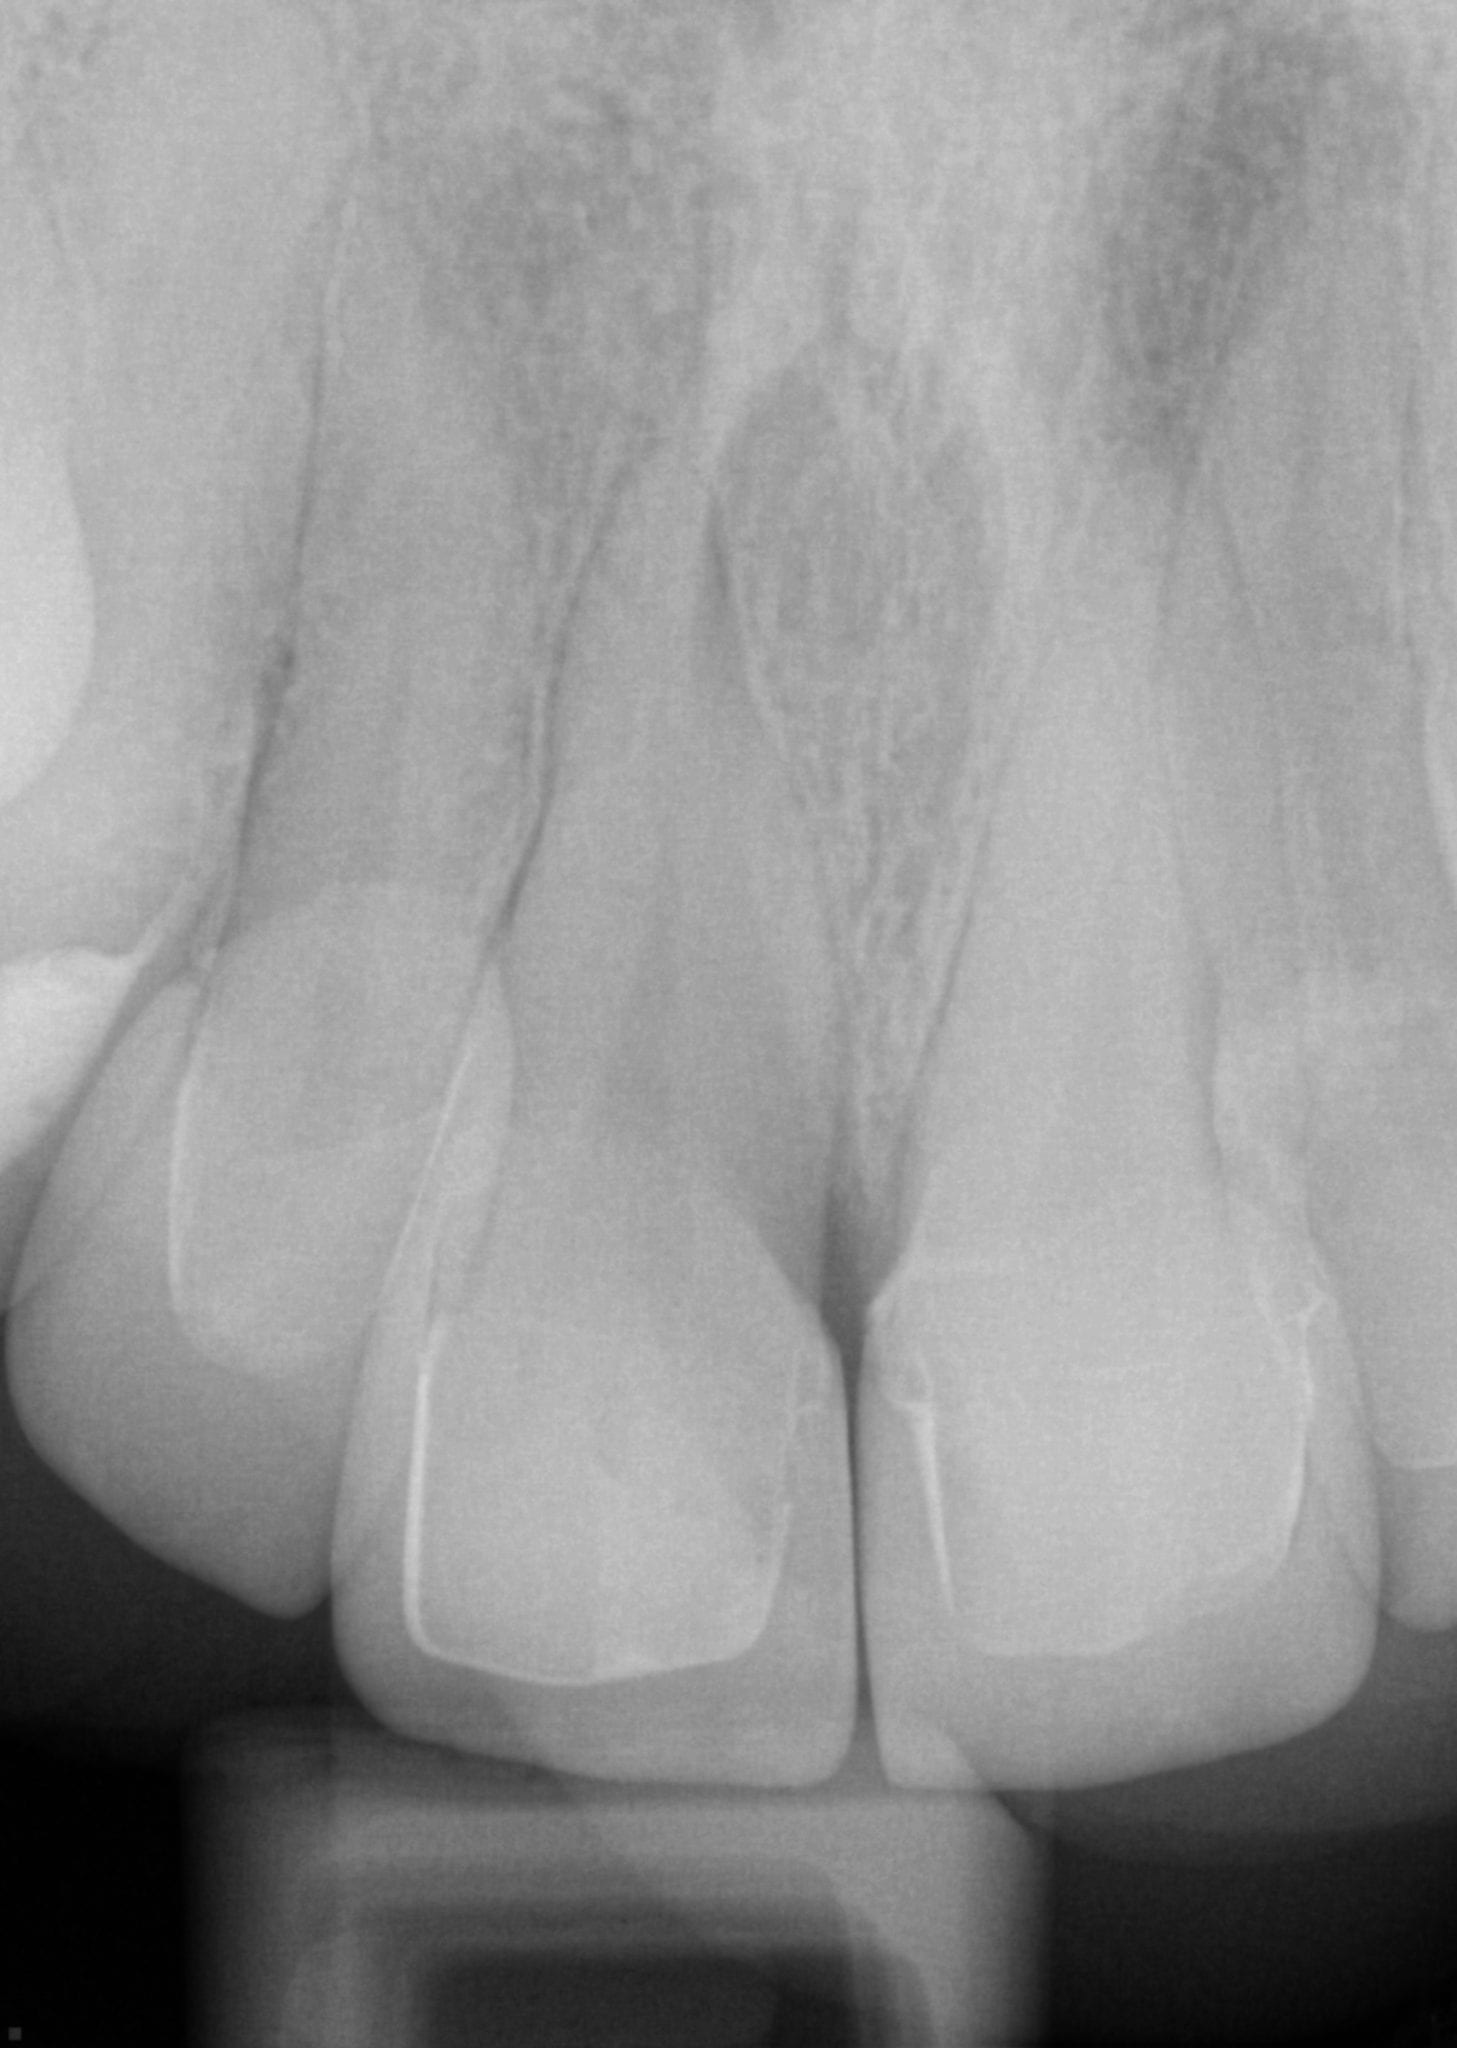

One Month Post Op with Radiographs